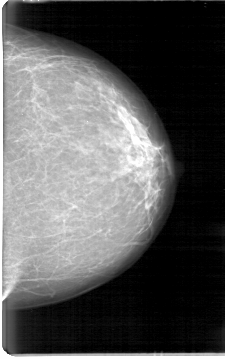

D_4090_1.LEFT_MLO

LEFT_MLO LINES 5251 PIXELS_PER_LINE 3181 BITS_PER_PIXEL 12 RESOLUTION 43.5 NON_OVERLAY